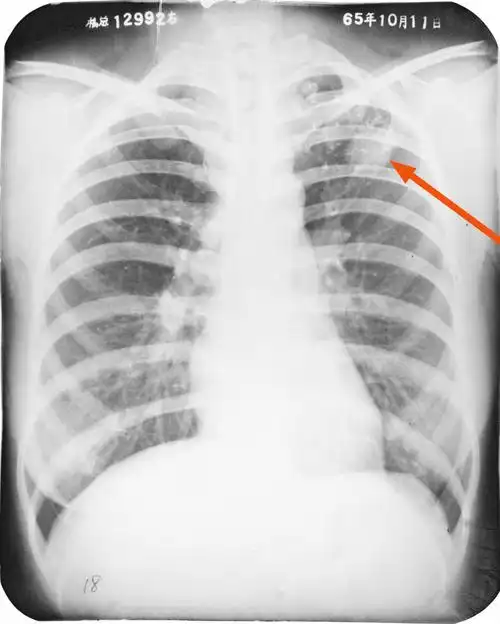

正常胸片 大叶性肺炎

症状不典型的大叶性肺炎

大叶性肺炎?但体征不明显,如图